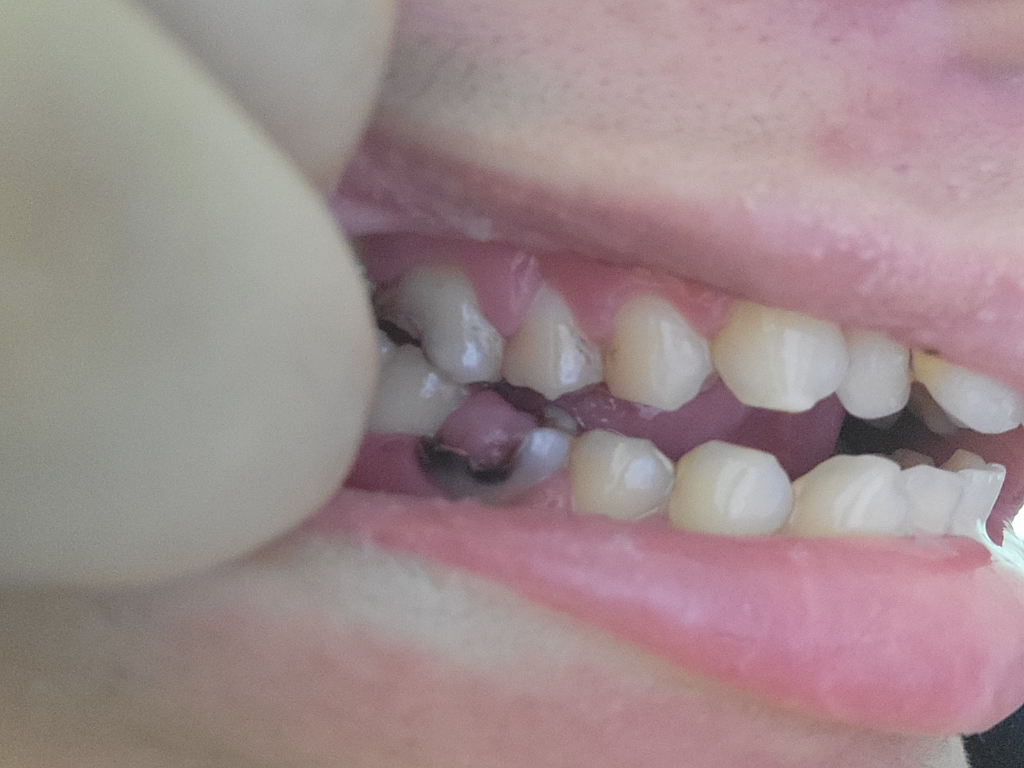

치과 9월갔는데 안늦것가요..

이빨이이상태데 근데엄마치과를9월갔다는데

9월갔면늦는것가요아니면 안늦었나요

• 1번 째 사진

현재 상태가 치아가 많이 썩어 거의 다 없어진 상태입니다. 가능한 치과 가는 것이 좋습니다.

사진으로 보이는 충치는 매우 넓기 때문에 신경치료를 동반한 크라운 ㅣ치료가 필요할수 있ㅅ브니다.

일단 진통제로 통증을 조절하셔야됩니다. 사진으로만 봐도 치아 상태가 많이 안좋아 보입니다. 빨리 치과에 가셔서 치료를 받으시는게 좋을것같습니다.